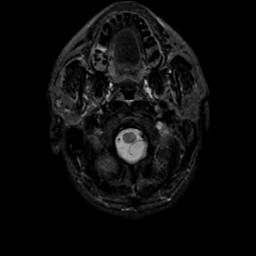

MR Study #22, December 1, 1991 -- Slice #2